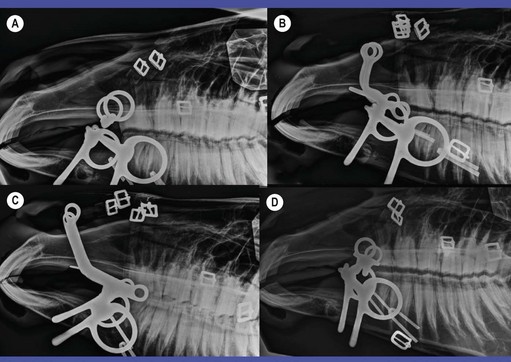

image

Fig. 3.17 Four overcheck systems used on racing Standardbreds. (A) Plain overcheck bit. (B) McKerron overcheck bit. (C) Crit Davis overcheck bit. (D) O’Mara leverage overcheck. All four driving bits are half-cheek snaffles.

Fig. 3.18 (A) Driving bridle with Ashleigh Elbow and sidecheck bits. (B) Horse bridled with Buxton and sidecheck bits. (C) Sidecheck rein attached to O ring snaffle driving bit.

Fig. 3.19 Lateral radiographs of overcheck bits in horses’ mouths. (A) Plain overcheck bit. (B) Crit Davis overcheck bit. (C) Crabb overcheck bit. (D) Burch overcheck bit. All four driving bits are half-cheek snaffles.

The plain overcheck bit (Figs 3.16G, 3.17A & 3.19A) is a very small straight bar bit. However, there are many other types, varying widely in severity (Fig. 3.16). Some racing overchecks, like the McKerron (Figs 3.16A & 3.17B), Crit Davis (Figs 3.16C, 3.17C & 3.19B), and Crabb (Figs 3.16D & 3.19C), listed in increasing order of severity, are used in combination with nose straps to prevent horses from leaning into their check reins.1,29 Potentially even more severe is the Burch overcheck (Figs 3.16B & 3.19D), which is shaped so as to press directly into the hard palate.

The combination of forces applied by the driving and check reins can place marked stress on a horse’s mouth, and one must be aware of the type of overcheck used when caring for a horse’s teeth and mouth. For example, the hard palate should be examined carefully for injury in a harness-racing horse who performs poorly when checked with a McKerron, Hutton, Burch, Crit Davis, or Crabb bit. If the palate is sore, one should consider recommending a change to a chin chain or leverage overcheck.1

Removal of wolf teeth, careful floating and rounding of the upper premolars and removing sharp edges from upper canine teeth are of special importance whenever overchecks are used.1,30 The upper canines are placed more caudally than the lower canines thus providing less space for the overcheck bit than for the driving bit. The overcheck bit may be forced backwards, especially if the horse’s head is checked very high, pinching the gums against the teeth. Even leverage overchecks can force a horse’s cheeks against upper points or caps.